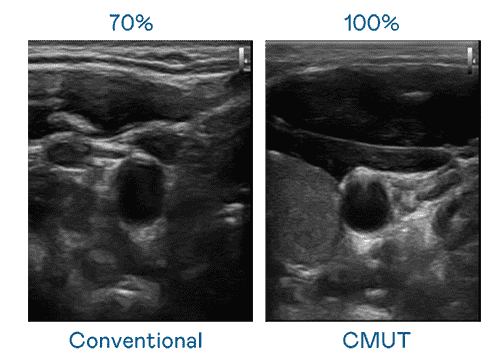

CMUT 技术是一种用电容式微机电元件来产生超音波讯号的技术。。。与传统 PZT 压电式技术相比,,CMUT 频宽增加 30%,,,,更宽频的超音波讯号让影像解析度大幅提升,,,,是实现高影像品质医疗超音波扫描、、、、促进精准医疗发展的关键技术。。。。

大频宽带来超清晰影像

超音波影像的解析度高低,,,首先取决于探头能发出的讯号频宽。。。。william威廉中文官网 CMUT 可提供高清晰的超音波讯号,,提供高频宽、、高灵敏度、、影像纹理细节更高的超音波影像,,,协助医护人员缩短影像判读时间及利用精准的医疗影像进行诊断。。。